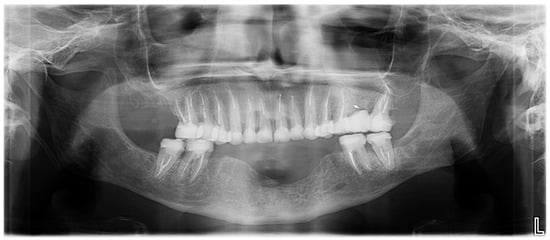

Figure 3.

Panoramic radiograph before treatment.

Extraoral examination revealed an unaesthetic smile, radiation-induced caries (Figure 1A), and mandibular retrognathia following carcinoma resection. The occlusal vertical dimension (OVD) was slightly reduced. Intraoral examination showed extensive decay in the remaining teeth (17 to 27, 36, 37, 46, and 47), with most being painful to percussion and highly sensitive to cold. Compromised restorations were noted in teeth 17, 16, 14, and 26 (Figure 2). The gingiva was inflamed and extremely sensitive, and the alveolar ridge in the mandibular incisal region was severely resorbed. Radiographic examination confirmed that 26 and 17 were non-restorable due to advanced root decay and periodontal disease (Figure 3).